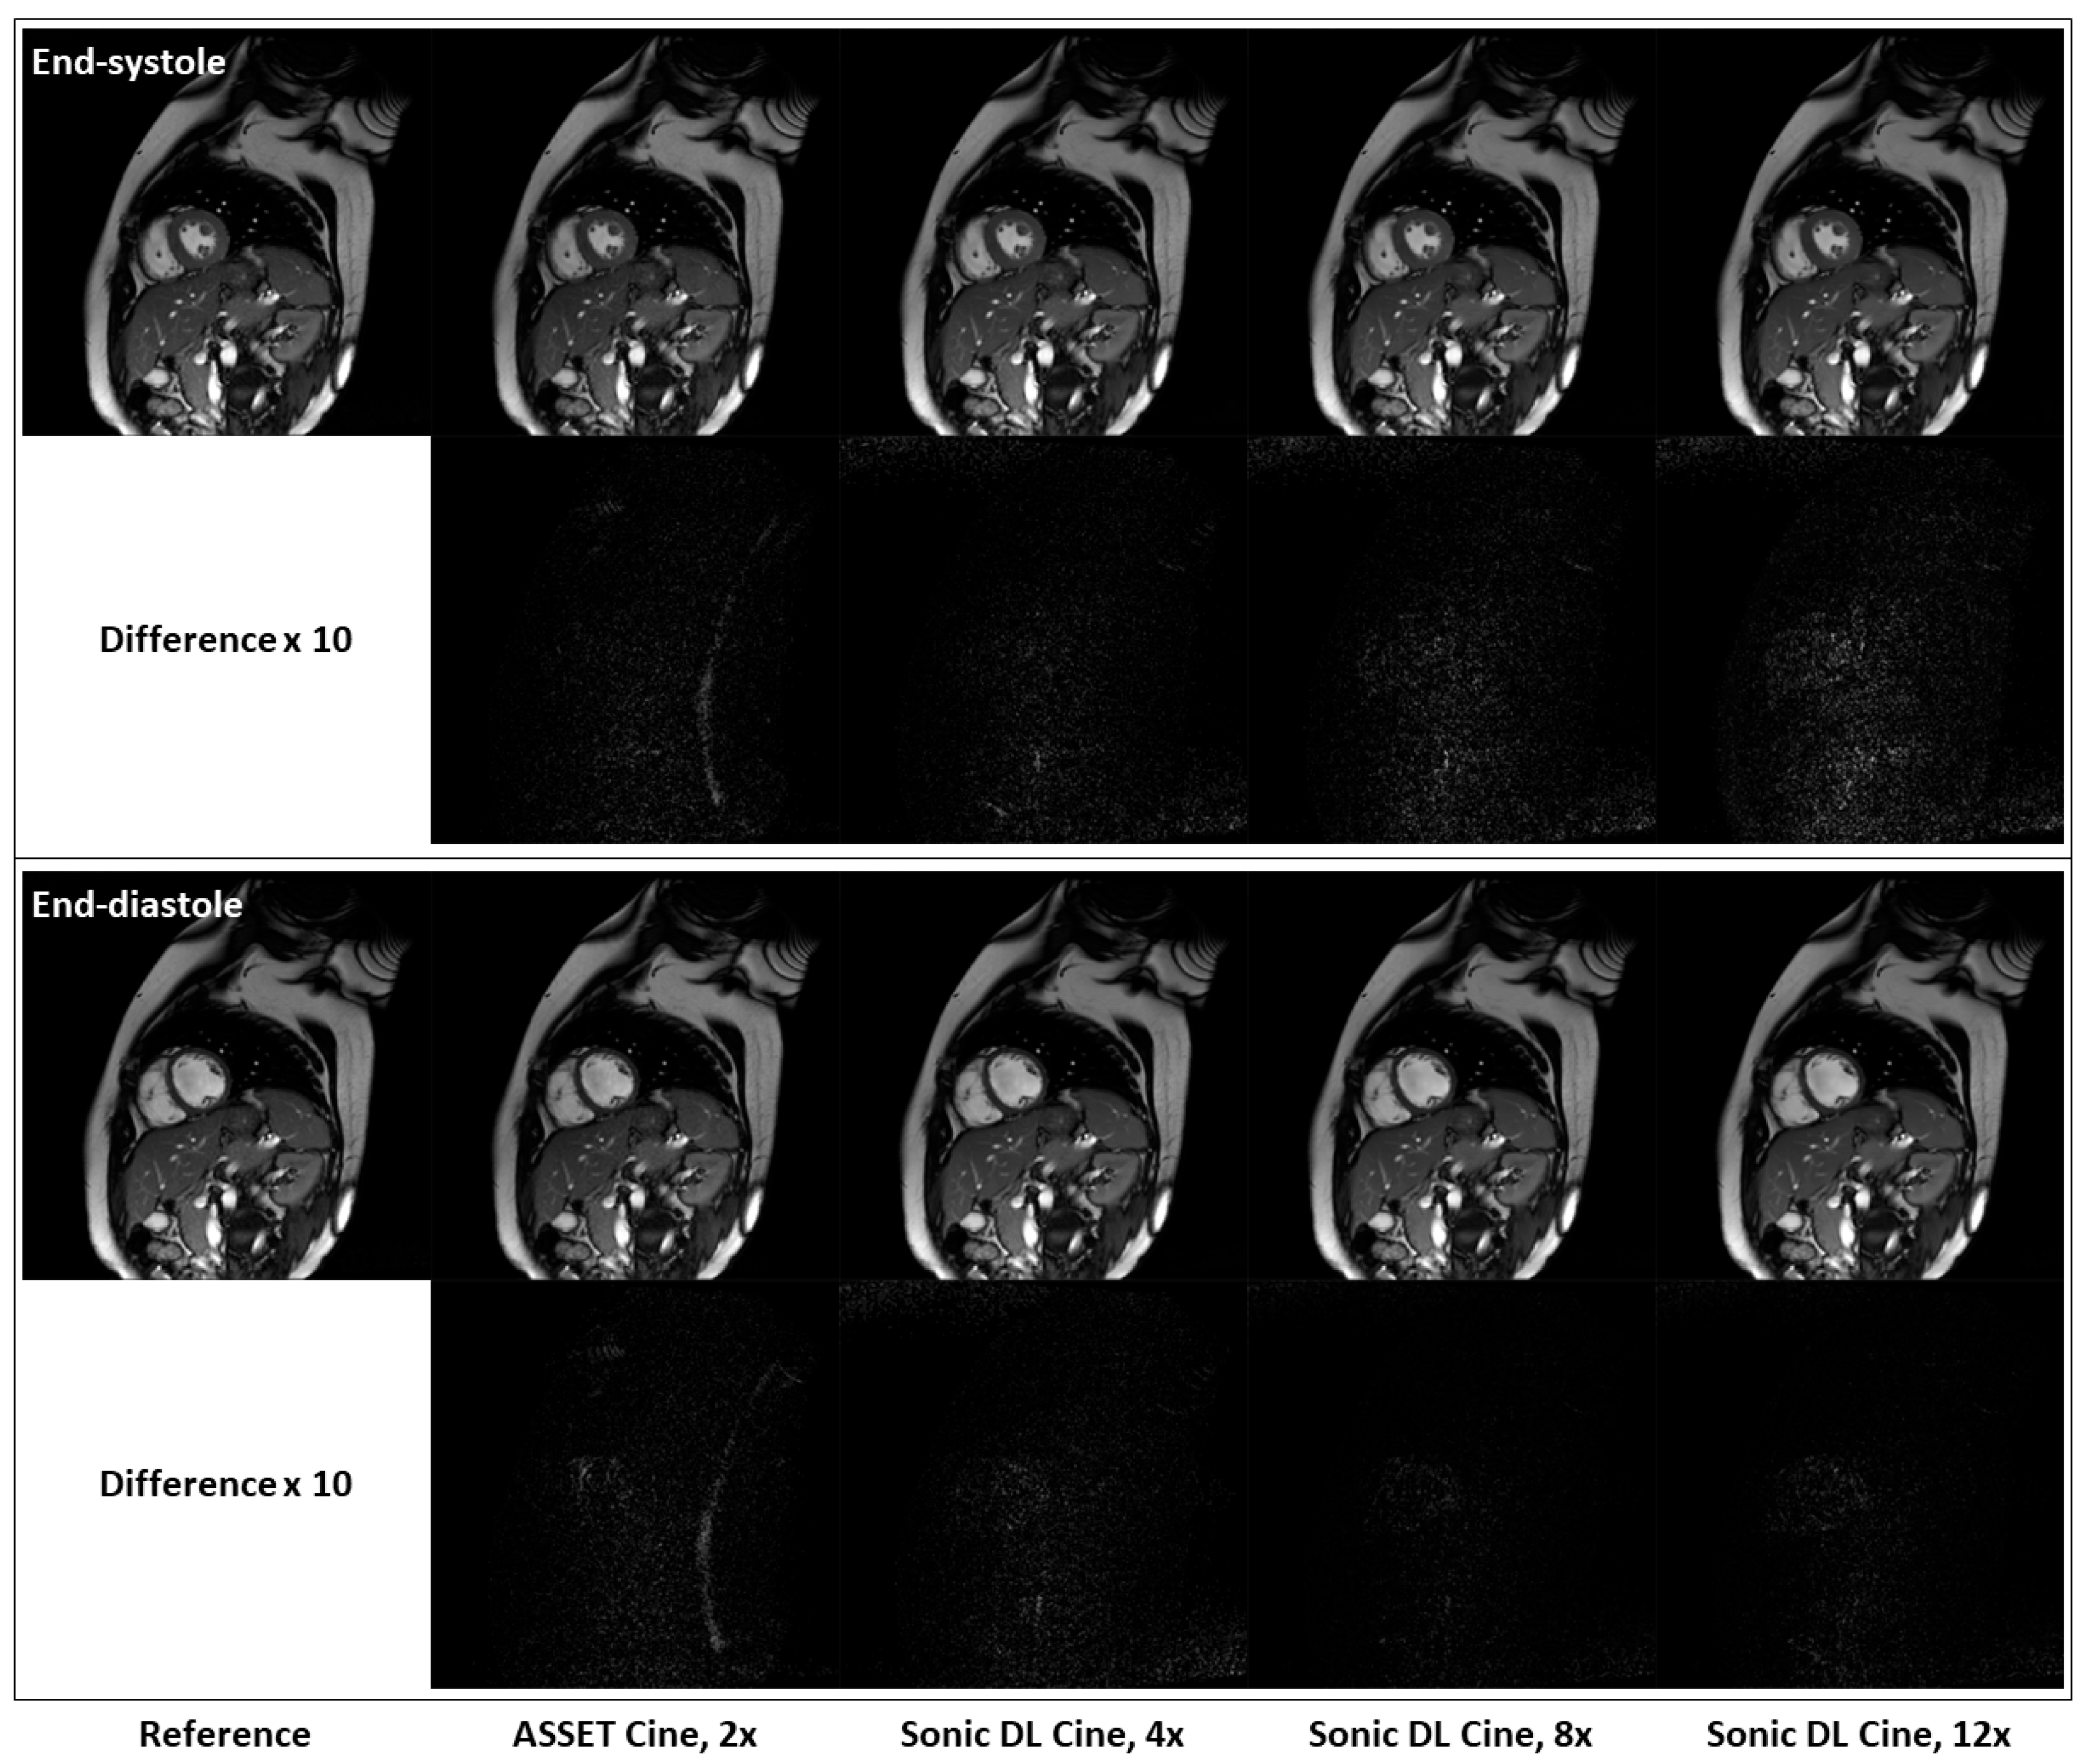

Figure 5 shows fully sampled and retrospectively under-sampled cine images from a healthy volunteer in the short-axis plane. At both end-systole and end-diastole phases, Sonic DL Cine-reconstructed images exhibit comparable SNR, contrast, and sharpness to both ASSET (acceleration factor = 2) and fully sampled cine images. Difference maps between the under-sampled and fully sampled images also confirm that Sonic DL Cine can reconstruct high-quality cine images from highly under-sampled k-space data with minor discrepancies from the fully sampled reference images. The difference between the under-sampled and fully sampled images is more visible when high acceleration (e.g., 12-fold acceleration) is applied. Additionally, retrospectively under-sampled and fully sampled cine images acquired on two-chamber, three-chamber, and four-chamber planes from representative subjects are shown in Figure 6. From all these different planes, Sonic DL Cine images closely match ASSET (acceleration factor = 2) and fully sampled cine images in terms of SNR, sharpness, and contrast, which is also demonstrated by difference maps between under-sampled and fully sampled images. Increased acceleration factors make the difference between Sonic DL Cine and fully sampled reference images more visible.

Figure 5.

Representative fully sampled and retrospectively under-sampled cine images from the short-axis plane. Retrospectively under-sampled cine images with ASSET (acceleration factor = 2) and Sonic DL Cine (acceleration factors = 4, 8, and 12) are compared to the fully sampled reference at both end-systole and end-diastole phases. Difference maps, amplified by a factor of 10, between the under-sampled and fully sampled cine images are also calculated.